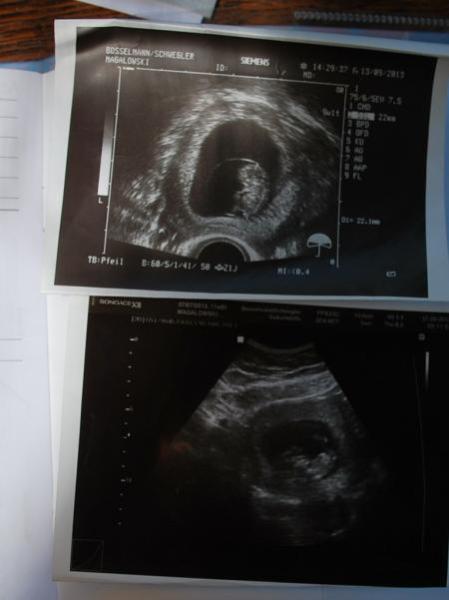

So ich bin immernoch in Deutschland und hatte Freitag schon den zweiten Arzttermin, dem Krümelchen geht es immernoch blendend und es tobt fleißig in meinem Bauch herum und ist nicht grade kommunikativ bei US Terminen, wir haben es fünf Minuten munter turnen und nach der Nabelschnur greifen sehen, aber stillhalten fürs Foto war nicht drin, also gibts nur ein verschwommenes Bild von einem kleinen "irgendwas" wie meine FA sagte :) Hab mal ne kleine Collage gebastelt und freu mich schon auf meinen ersten großen US in UK :) Der wird dann wohl so um die 16. Woche herum erfolgen :) Ich bin jetzt inzwischen in der 13. Woche bei 12+3 und ET bleibt der 13.04. :)

Das untere ist das Bild von 2. US - aber wie man sieht, sieht man nichts :)